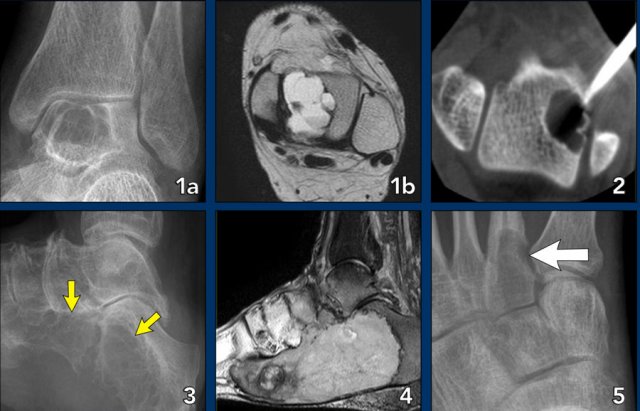

Foot lesions

Here some typical examples of bone tumors in the foot:

1. Geode or subchondral cyst in the navicular bone

2. Geode or subchondral cyst in the tarsal bone

3. Chondroblastoma in the tarsal bone

4. X-ray and MRI of a chondroblastoma in the tarsal bone

5. Chondroblastoma in the tarsal bone

1. Aneurysmal bone cyst in the tarsal bone

2. Chondroblastoma in the tarsal bone

3. Chondromyxoid fibroma (CMF) in the calcaneus

4. Same patient MRI

5. CMF in the second metatarsal bone